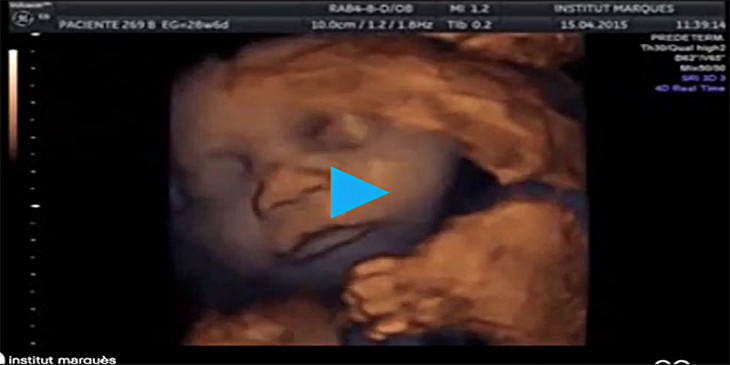

စပိန္ႏိုင္ငံက မိခင္တဦးရဲ႕ သားအိမ္ထဲမွာ သီတင္းပတ္ ၁၆ ပတ္ရွိၿပီျဖစ္တဲ့ သေႏၶသားေလာင္း ကေလးငယ္ဟာ ဂီတသံနဲ႔အတူ သီဆိုကႏိုင္တယ္ဆိုတာကို ျပသႏိုင္ခဲ့တယ္လို႔ ၿဗိတိန္အေျခစိုက္ ေဒးလီးေမရာသတင္းမွာ ေဖာ္ျပပါတယ္။

အံ့ၾသစရာေကာင္းတဲ့ ဒီဗီြဒီယိုဖိုင္မွာေတာ့ သေႏၶသားကေလးငယ္ဟာ မိခင္အဂၤါကတဆင့္ ထုတ္လႊတ္တဲ့အသံကို ၾကားႏိုင္ၿပီး ပါးစပ္ကို လႈပ္ရွားပံုနဲ႔ ဂီတသံနဲ႔အတူ လႈပ္ရွားပံုေတြကို ခ်စ္စရာေကာင္းတဲ့ သံုးဘက္ျမင္ပံုရိပ္ေတြအျဖစ္ ေတြ႔ျမင္ႏိုင္ပါတယ္။

ၿဗိတိန္ႏိုင္ငံက ေဆးပညာဆိုင္ရာ အာလ္ထရာေဆာင္းဂ်ာနယ္က ေဆးပညာရွင္ေတြဟာ အထူးျပဳလုပ္ထားတဲ့ ကိရိယာကို မိခင္ရဲ႕ အဂၤါကေနတဆင့္ ထိုးသြင္းၿပီး ဂီတကို နားဆင္ေစခဲ့တာ ျဖစ္တယ္လို႔ ဆိုပါတယ္။

မိခင္၀မ္းဗိုက္တြင္း တစ္႐ႉးေတြက ထုတ္လႊင့္လိုက္တဲ့ ဂီတသံကို စုပ္ယူထားလိုက္တာျဖစ္ၿပီး အဲဒီအသံကို တဆင့္ျပန္လည္ ထုတ္လႊတ္တာ ျဖစ္တယ္လို႔ သတင္းမွာ ေဖာ္ျပပါတယ္။

အဲဒီသုေတသနမွာ သေႏၶသားေလာင္းေတြရဲ႕ ၈၇ ရာခိုင္ႏႈန္းဟာ သူတို႔ရဲ႕ပါးစပ္ ဒါမွမဟုတ္ လွ်ာကို အလိုရွိသလို ေရြ႕လ်ားႏိုင္တယ္လို႔ ေျပာပါတယ္။

ဘာစီလိုနာနဲ႔ မီလန္ၿမိဳ႕ေတြက ေဆးပညာဆိုင္ရာ ပညာရွင္ေတြက ခုလိုေတြ႔ရွိမႈဟာ ေမြးဖြားၿပီးေနာက္ပိုင္း ကေလးငယ္ရဲ႕ အသံစြမ္းရည္ဆိုင္ရာ ဖြံ႔ၿဖိဳးတိုးတက္မႈကို အေထာက္အကူ ျပဳႏိုင္လိမ့္မယ္လို႔ ေျပာပါတယ္။

အဲဒီသုေတသနမွာ ပါ၀င္တဲ့ ေဒါက္တာ မာရီဆာလိုပက္ဇ္တီဂ်န္က အခုေတြ႔ရွိမႈဟာ သေႏၶသားေလာင္းက မိခင္ရဲ႕ အဂၤါမွတဆင့္ လႊင့္ထုတ္တဲ့ ဂီတသံကို မေမြးခင္တည္းက ၾကားႏိုင္တယ္ဆိုတာ ေတြ႔ရွိရၿပီး သေႏၶသားေလာင္းဟာ ထုတ္လႊင့္လုိက္တဲ့ ဂီတကို တုံ႔ျပန္ႏိုင္တဲ့အတြက္ တနည္းအားျဖင့္ေျပာရရင္ မေမြးခင္တည္းက သင္ယူေလ့လာမႈ စတင္ေနတာ ျဖစ္တယ္လို႔ ေျပာပါတယ္။